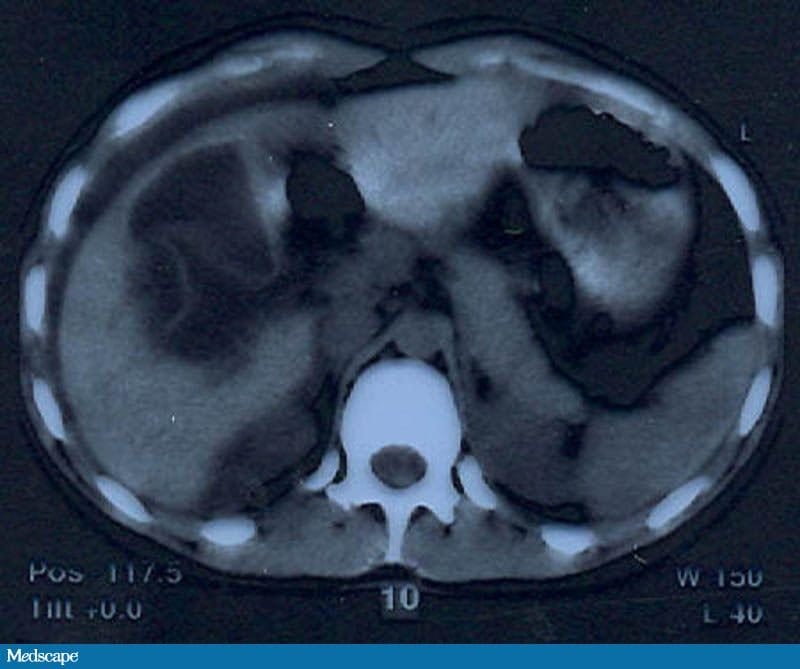

Uma radiografia do abdome em posição ortostática mostra um padrão de gases intestinais inespecífico, sem pneumoperitônio. É feita uma ultrassonografia por suspeita de possível doença da vesícula biliar; o exame revela uma grande zona hipoecoica hepática com margens irregulares e uma pequena quantidade de líquido livre circundando o fígado. Na sequência, é feita a tomografia computadorizada (TC) do abdome (Figuras 1 e 2).

Figura 2.